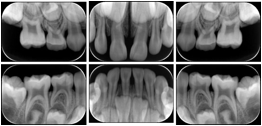

2. A patient requests cosmetic surgery to enhance their facial appearance. The case requires consultation between an orthodontist in New York and an oral surgeon in California. The cephalometric series of 2D projections constructed from a volumetric CT data set that is used for the discussion is arranged by a Structured Display for transfer between the two practitioners.

Cephalometric Series Structured Display

Figure OO-2. Cephalometric Series Structured Display